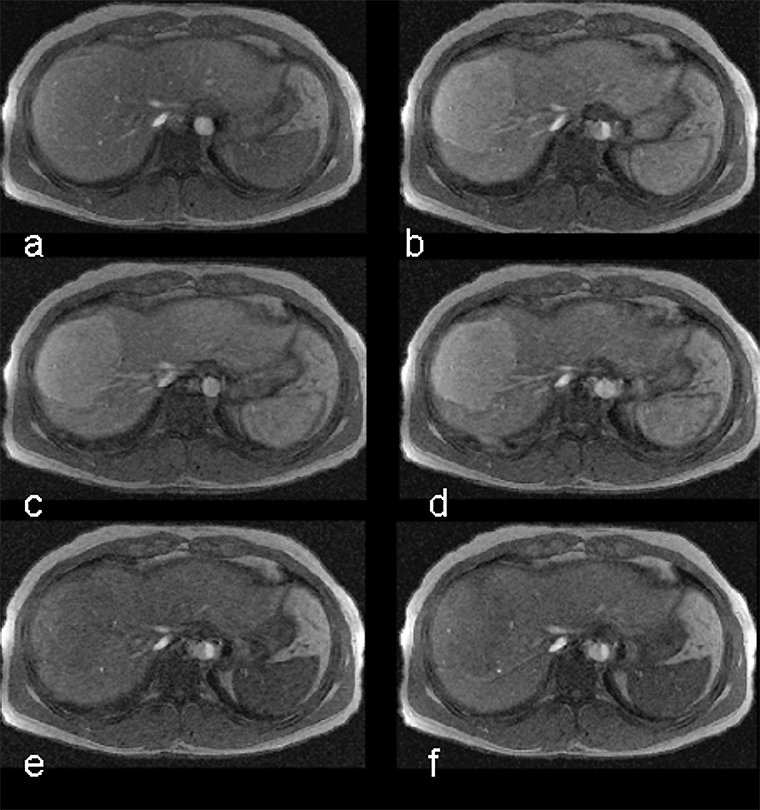

Mn-DPDP (Figure 13-16) is a positive multipurpose agent ta­ken up by, e.g., the he­pa­to­cytes [⇒ Rummeny 1997]. The contrast enhancement seems to be connected to a limited release of manganese ions. The enhancement is long last­ing and can be achieved with low doses. While on the market for liver applications, mangafodipir was the preferred agent in patients with kidney problems. Oral or intravenous MnCl2 can have a similar effect.

Figura 13-16:

The uptake of Mn-DPDP (mangafodipir) in the liver relies on the ability of hepatocytes to excrete metal ions. Manganese separates from the DPDP-complex and is taken up by the hepatocytes.

T1-weighted GRE images. (a) The metastases are well delineated 15 minutes after the injection, and (b) even 24 hours after administration some of the contrast agent remains.